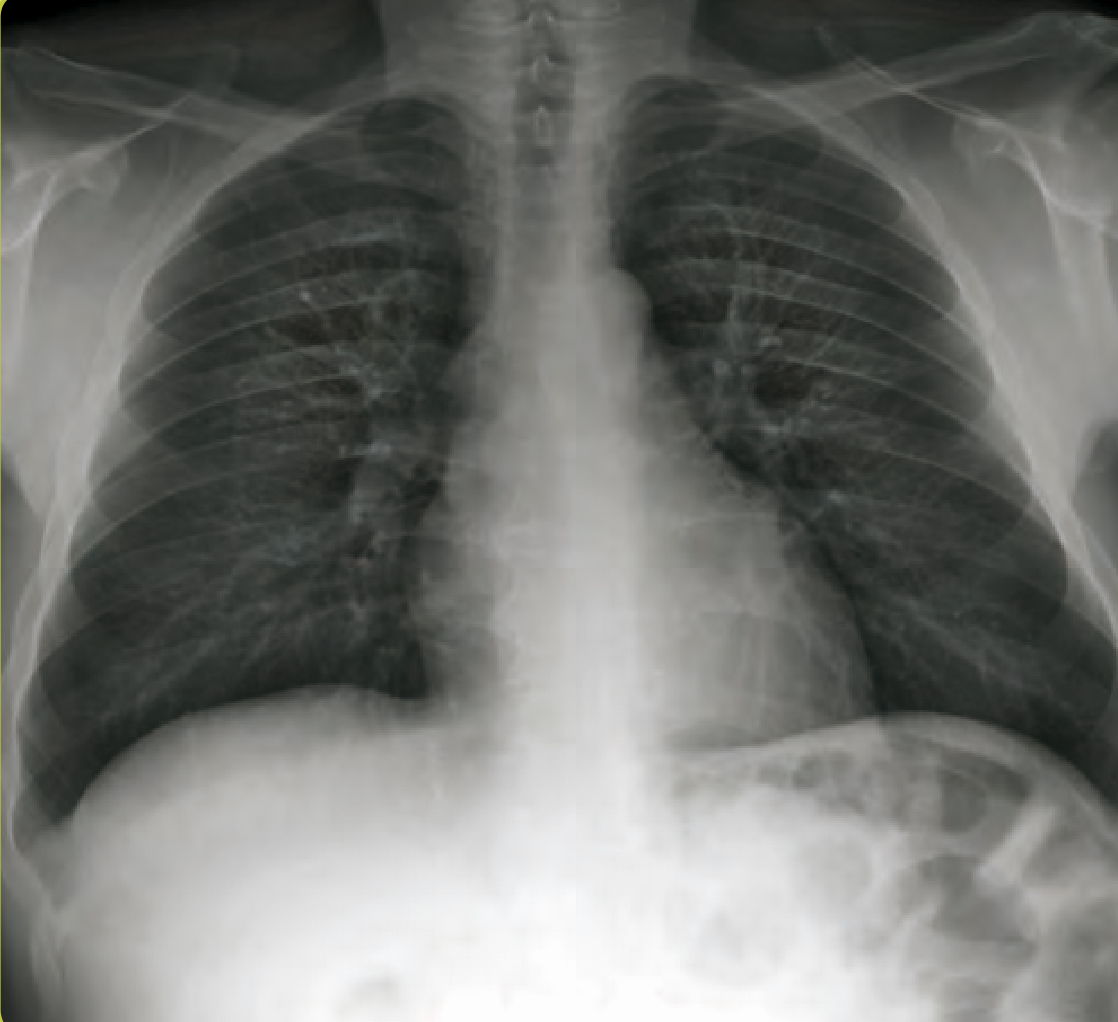

21

Q

Что отмечено стрелками на снимке?

Что такое линии Кёрли? Какие типы Вы знаете?

Интерстициальные заболевания легких характеризуются ретикулоузловой картиной паутиноподобных затенений из-за наложения отечных междольковых перегородок + мелкоочаговых затенений с четкими границами.

A

Поверхностные лимфатические протоки легких, в даном случае с признаками застоя походу междольковых перегородок.

На снимке становятся видны в виде линий, которые мы называем линиями Керли. В даном случае линии Керли типа В (короткие линейные затенения 1-2 см. в сублевральной области (на периферии полей легких) в нижнем или среднем отделе легких.

Линии Керли типа А более длинные (до 5 см.), идут от корней легких в верхней доле.

Есть карточка с делением легких на отделы (отделы - не доли, а как бы три этажа легочного поля, чтобы более понятно описывать локализацию структур именно на снимке).